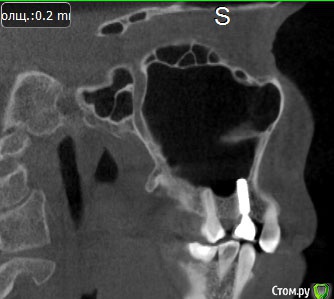

Lyuba Опубликовано 11 ноября, 2014 Автор Поделиться Опубликовано 11 ноября, 2014 сегодня сняли в очередной раз. версии:- из-за импланта, который немного выходит в гайморову пазуху- слишком широкая коронка и создает непомерную нагрузку на имплантно это увы, только версии.мрт подойдет? Ссылка на комментарий

Lyuba Опубликовано 5 января, 2015 Автор Поделиться Опубликовано 5 января, 2015 С наступившим Новым Годом! Желаю всем побольше счастья и поменьше проблем! )) Прошу прощения, что опять мучаю Вас вопросами, но очень хочется разрешить проблему с зубами, поскольку постоянные ноющие боли достали (((((несмотря на то, что коронку с импланта сняли уже 2 месяца назад и поначалу было вроде бы полегче, боли сохранились.Сейчас я Швейцарии с консультировалась с имплантологами двух клиник (Швейцария и Германия).Они говорят, что имплант установлен на 2-3 мм в гайморову пазуху, что является бесспорной ошибкой хирурга, и его нужно извлекать.В то же время 100% гарантии, что боли дает именно имплант, а не соседний 6й зуб нет. Аргументация за то, что имплант "проблемный" - гайморова пазуха.что проблема в соседнем 6м зубе : пломба недалеко от пульпы. Но: два месяца назад пломбу сменили пульпа не вскрыта, кариеса не было... Сегодня делали рентген 6ки... - измененений у корня зуба нет, зуб с адекватной реакцией "живого зуба" на электрические токи и холодовой тест.Один из врачей сказал, что может быть, это проблема периодонта (какие-то небольшие разрежения), но снаружи все очень прилично выглядит.... Можно ли как-то ТОЧНО установить, в чем проблема - в импланте или соседнем зубе?не хочется "методом исключения" депульпировать зуб или выпиливать имплант (и зашивать гайморову пазуху с последующей установкой костного материала).... Ссылка на комментарий

IvanK Опубликовано 5 января, 2015 Поделиться Опубликовано 5 января, 2015 Проблем с имплантатом нет.то, что имплантат в пазухе не является ошибкой. Признаков воспаления в пазухе нет. 3 Ссылка на комментарий

Lyuba Опубликовано 5 января, 2015 Автор Поделиться Опубликовано 5 января, 2015 Иван, зубы на витальность проверены в креслах аж трех стоматологов (холодовой тест и тест электричеством), сделаны 2КТ (Galileos и WhiteFox), сделаны прицельные рентгеновские снимки всех зубов на этой стороне, а проблема до сих пор не выявлена.У меня НЕТ ЦЕЛИ кого-то ОБВИНЯТЬ ИЛИ что-то УДАЛЯТЬ, но жить с постоянной ноющей болью годами как-то неприятно. Надеюсь, Вы меня понимаете. Перфорация гайморовой пазухи и инородное тело в ней - это НЕПРАВИЛЬНО. Клиентом ЛОРА я уже по этому поводу была после установки импланта. У некоторых пациентов это, может и не вызывает проблем, но вот лично у меня, к примеру, выведенный за верхушку канала пломбировочный материал дважды вызывал многолетние боли и периодонтит. А здесь имплант в гайморовой.Боли он может вызывать, даже если нет кисты. Как можно исключить то, что это имплант? Или установить, что это соседний зуб? или проблема с периодонтом?Может, перенести тему в раздел хирургии? 1 Ссылка на комментарий